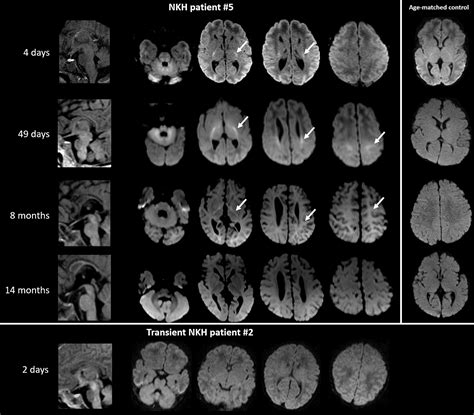

• Nonketotic Hyperglycinemia (NKH): This is the most severe form, often presenting in infancy. It is caused by a deficiency in the glycine cleavage system, leading to high levels of glycine in the brain and other tissues.

• Transient Hyperglycinemia of the Newborn: This type is typically benign and resolves on its own within the first few weeks of life. It is often associated with prematurity or other stress factors.